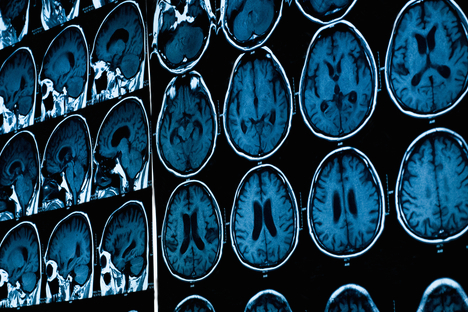

Researchers at Indiana University are conducting a study to determine exactly how marijuana affects the structure and function of the brain. Magnetic resonance imaging (MRI) is being employed to analyze 90 participants, all ages 18 to 35, comprised of current and former pot users, as well as those who have never used marijuana.

Participants will be asked to undergo tests of perception, memory and thinking, and report any issues they may be experiencing as a result of their pot use. The research team will then conduct connectivity analysis on the data culled from all three groups to determine the efficiency of communication between the brain regions. “I like to think of the brain as an electrical circuit,” said study co-leader Sharlene Newman, an associate professor at Indiana University and head of the school’s Brain Imaging Facility.

“If the insulation on the wires is not intact, you can get current leakage resulting in faulty communication,” Newman added. “If the connections between brain regions are faulty, then the functioning of the brain will be faulty or inconsistent. With the MRI techniques we will use, we will be able to examine the integrity of the insulation.”